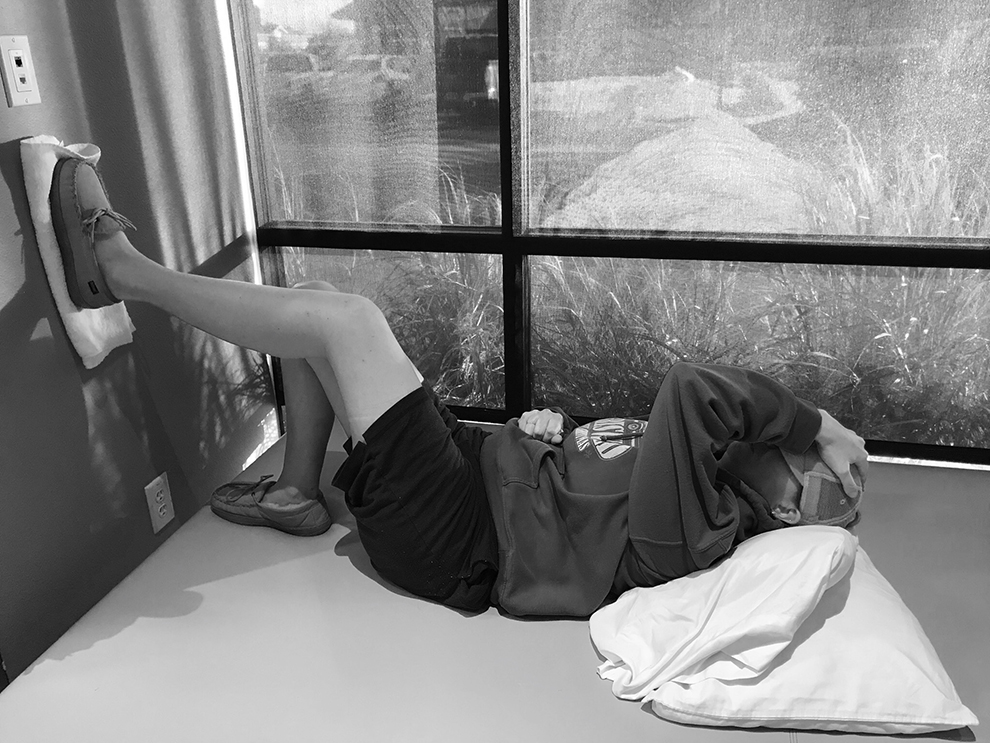

I have a transfer wheel chair. It helps soooo much. I am able to be up much longer than if I were just on crutches. I can cook a little. I can do a few things that I otherwise wouldn’t be able to do. I am not able to get into the shower yet (I was before surgery, but my knee isn’t allowed to bend far enough yet to sit down and twist through the door right now, and it’s down a set of stairs which I would maneuver on my tush, and already do the other full set of stairs into the loft)

Physical Therapy is by far my happy place. Even though I have spent many sessions in tears. I know 100% that the harder I work, the better I follow directions…. the better I will be in the end. And the stronger I will be. I lost 80% of the use of my upper leg muscles and most of my leg has atrophied, but just last week I was able to flex my quad muscle on my own…. that accomplishment was major and the sense of accomplishment from just that tiny little thing was incredible. I lucked out and have the most amazing team working with me. The atmosphere is uplifting. And even if I’ve crying, they are still incredibly encouraging. Plus it’s a time that I get to hang out with my son (I have felt so left out from his daily life, and this is the time I get with him.) I have been told that I’m healing really well for my age. (I laugh at that every time I hear it, as I think they are (the surgeon mostly) used to 18 year olds coming back from this. )

Below are some pictures from my every day the last few months. Some might be a little much… so slow your scroll if you don’t want to see them.